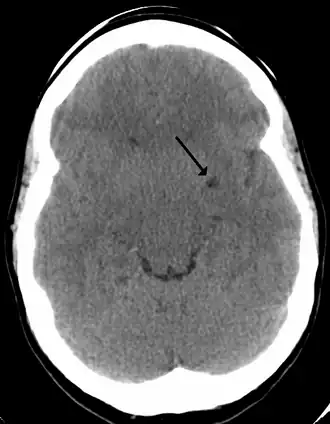

![]() A perivascular space as seen on CT | |

A perivascular space, also known as a Virchow–Robin space, is a fluid-filled space surrounding certain blood vessels in several organs, including the brain,[1] potentially having an immunological function, but more broadly a dispersive role for neural and blood-derived messengers.[2] The brain pia mater is reflected from the surface of the brain onto the surface of blood vessels in the subarachnoid space. In the brain, perivascular cuffs are regions of leukocyte aggregation in the perivascular spaces, usually found in patients with viral encephalitis.

In humans, perivascular spaces surround arteries and veins can usually be seen as areas of dilatation on MRI images. While many normal brains will show a few dilated spaces, an increase in these spaces may correlate with the incidence of several neurodegenerative diseases, making the spaces a topic of research.[4]